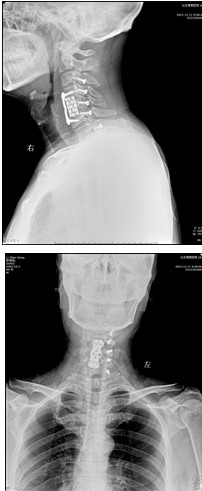

患者,男性,49岁,主因“行走不稳2个月伴右前臂麻木1个月”入院

2月前开始出现双下肢行走不稳,有踩棉花感,行走距离受限。1月前出现右侧前臂及手指麻木感。3周前诊断为“颈椎病”,保守治疗无改善,行走不稳症状加重

手术效果:术后当天下肢麻木无力症状即消失,术后1天,上肢麻木无力症状也好转。术后7天离床活动,自觉踩棉花感觉消失,下肢变得有力,可以正常速度上下楼,双手抓握力量明显增强,灵活性好。查体上肢肌力如屈指肌力、小指外展肌力恢复到5级,下肢小腿三头肌肌力恢复到5级。